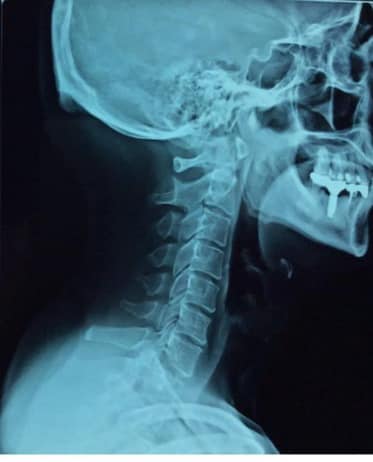

診斷: 1.頸椎後縱韌帶鈣化壓迫脊髓

2.左側C4C5壓迫嚴重之脊髓型頸椎病

3.C5C6;C6C7輕微脊髓型頸椎病 3.頸椎嚴重變形